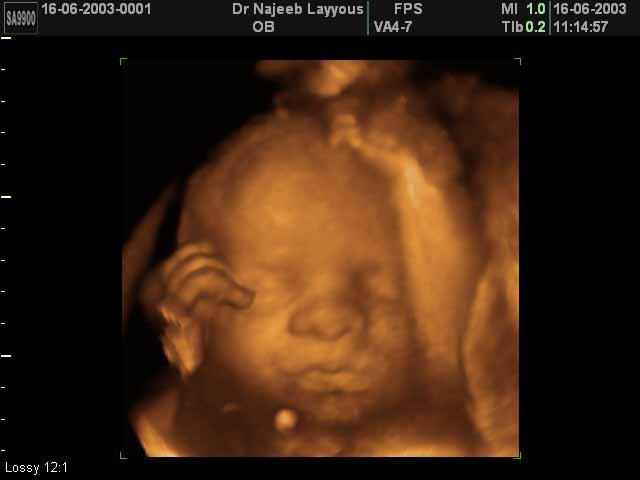

- صور لوجه الجنين في داخل الرحم

- صور جانبية لرأس الجنين

- تصرفات الجنين داخل الرحم

- أهمية التصوير بالموجات فوق الصوتية رباعي الابعاد في الحمل 4D ultrasound

صور لوجه الجنين بجهاز الالتراساوند ثلاثي الأبعاد | الدكتور نجيب ليوس